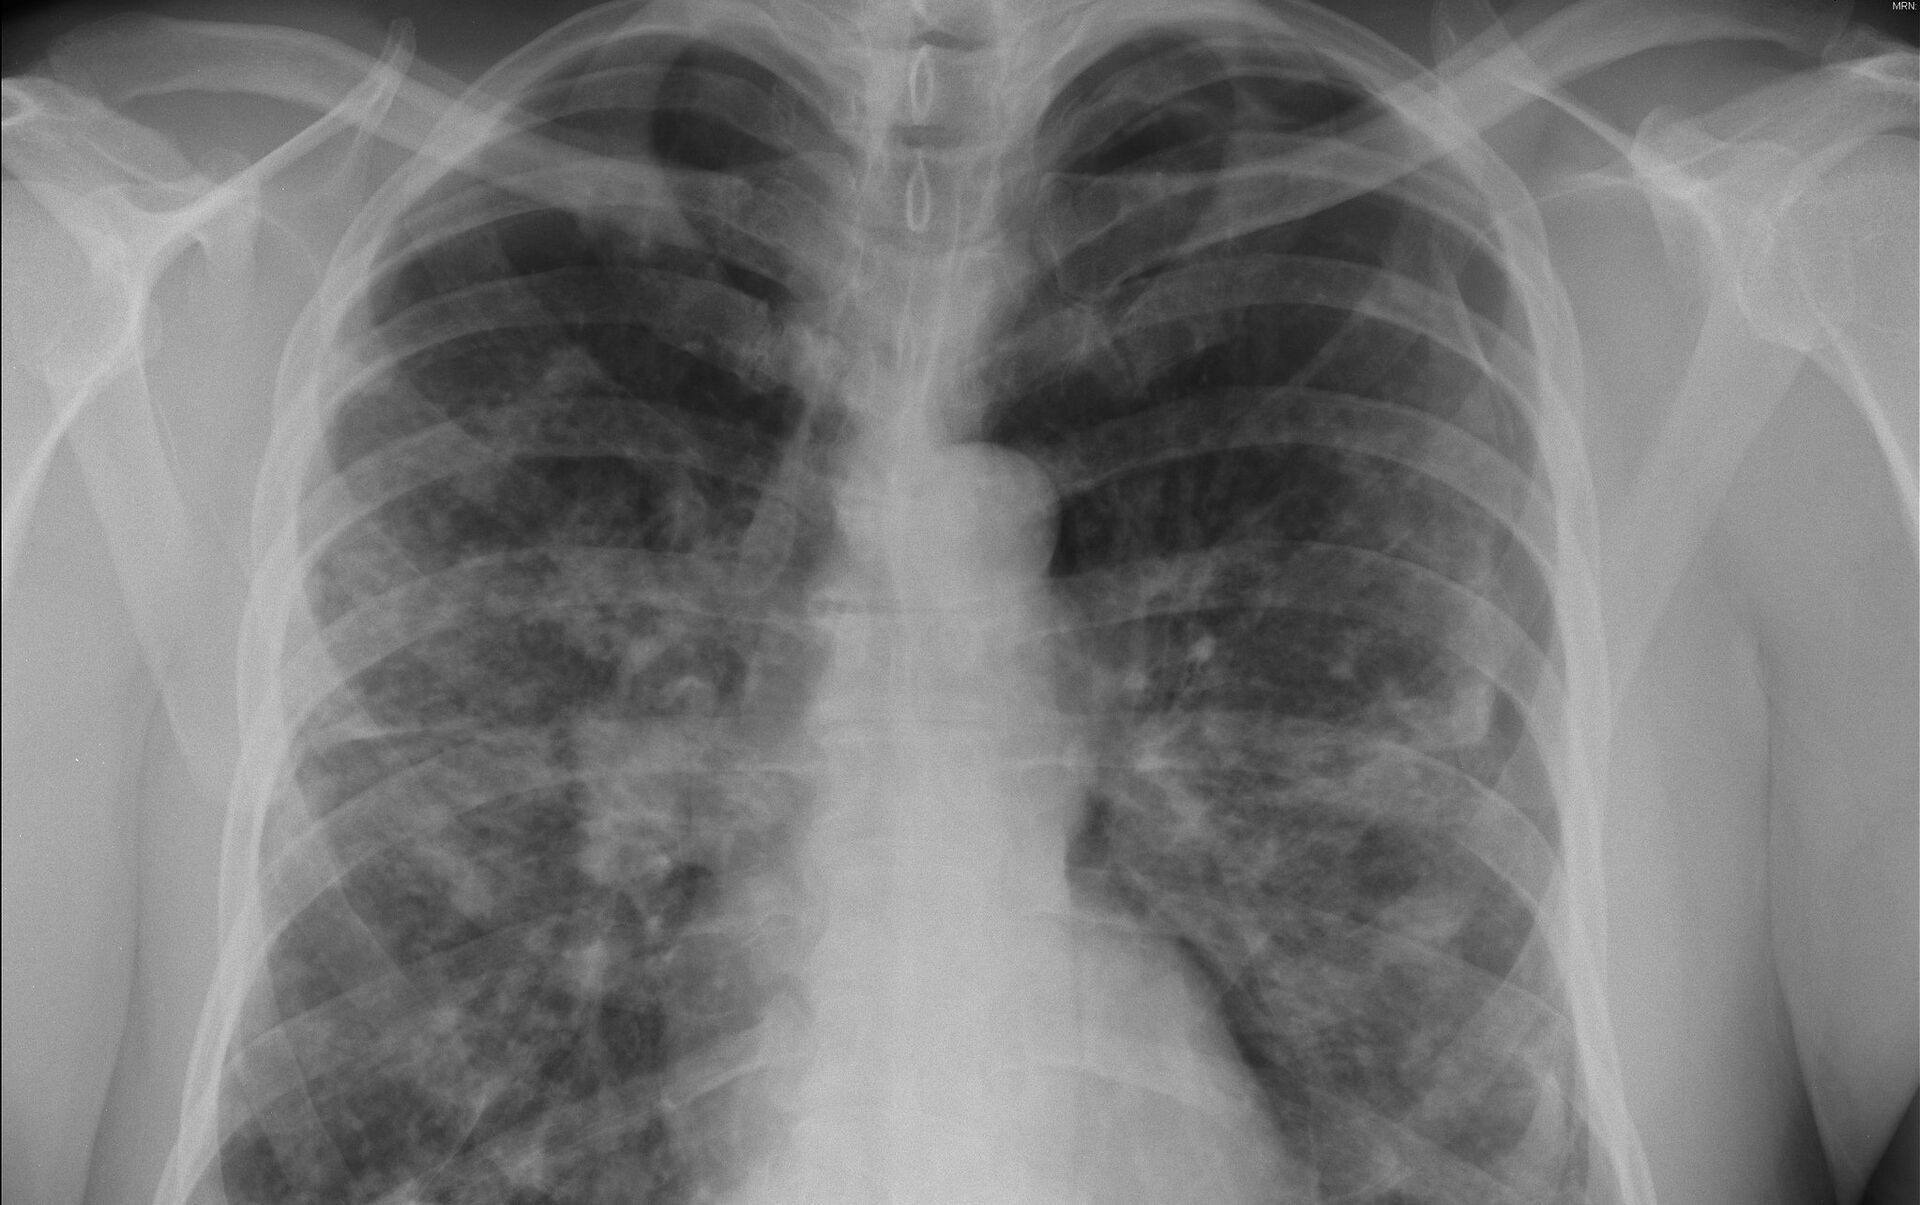

Este nuevo sistema puede ayudar a detectar el cáncer de pulmón de una manera rápida, eficiente y no invasiva, algo que hasta ahora era imposible.

El cáncer de pulmón es uno de los más mortíferos entre las enfermedades cancerosas. En Rusia se registran unos 60.000 casos de cáncer de pulmón al año. Y la posibilidad de detectarlo a tiempo podría ser la diferencia entre la vida y la muerte.